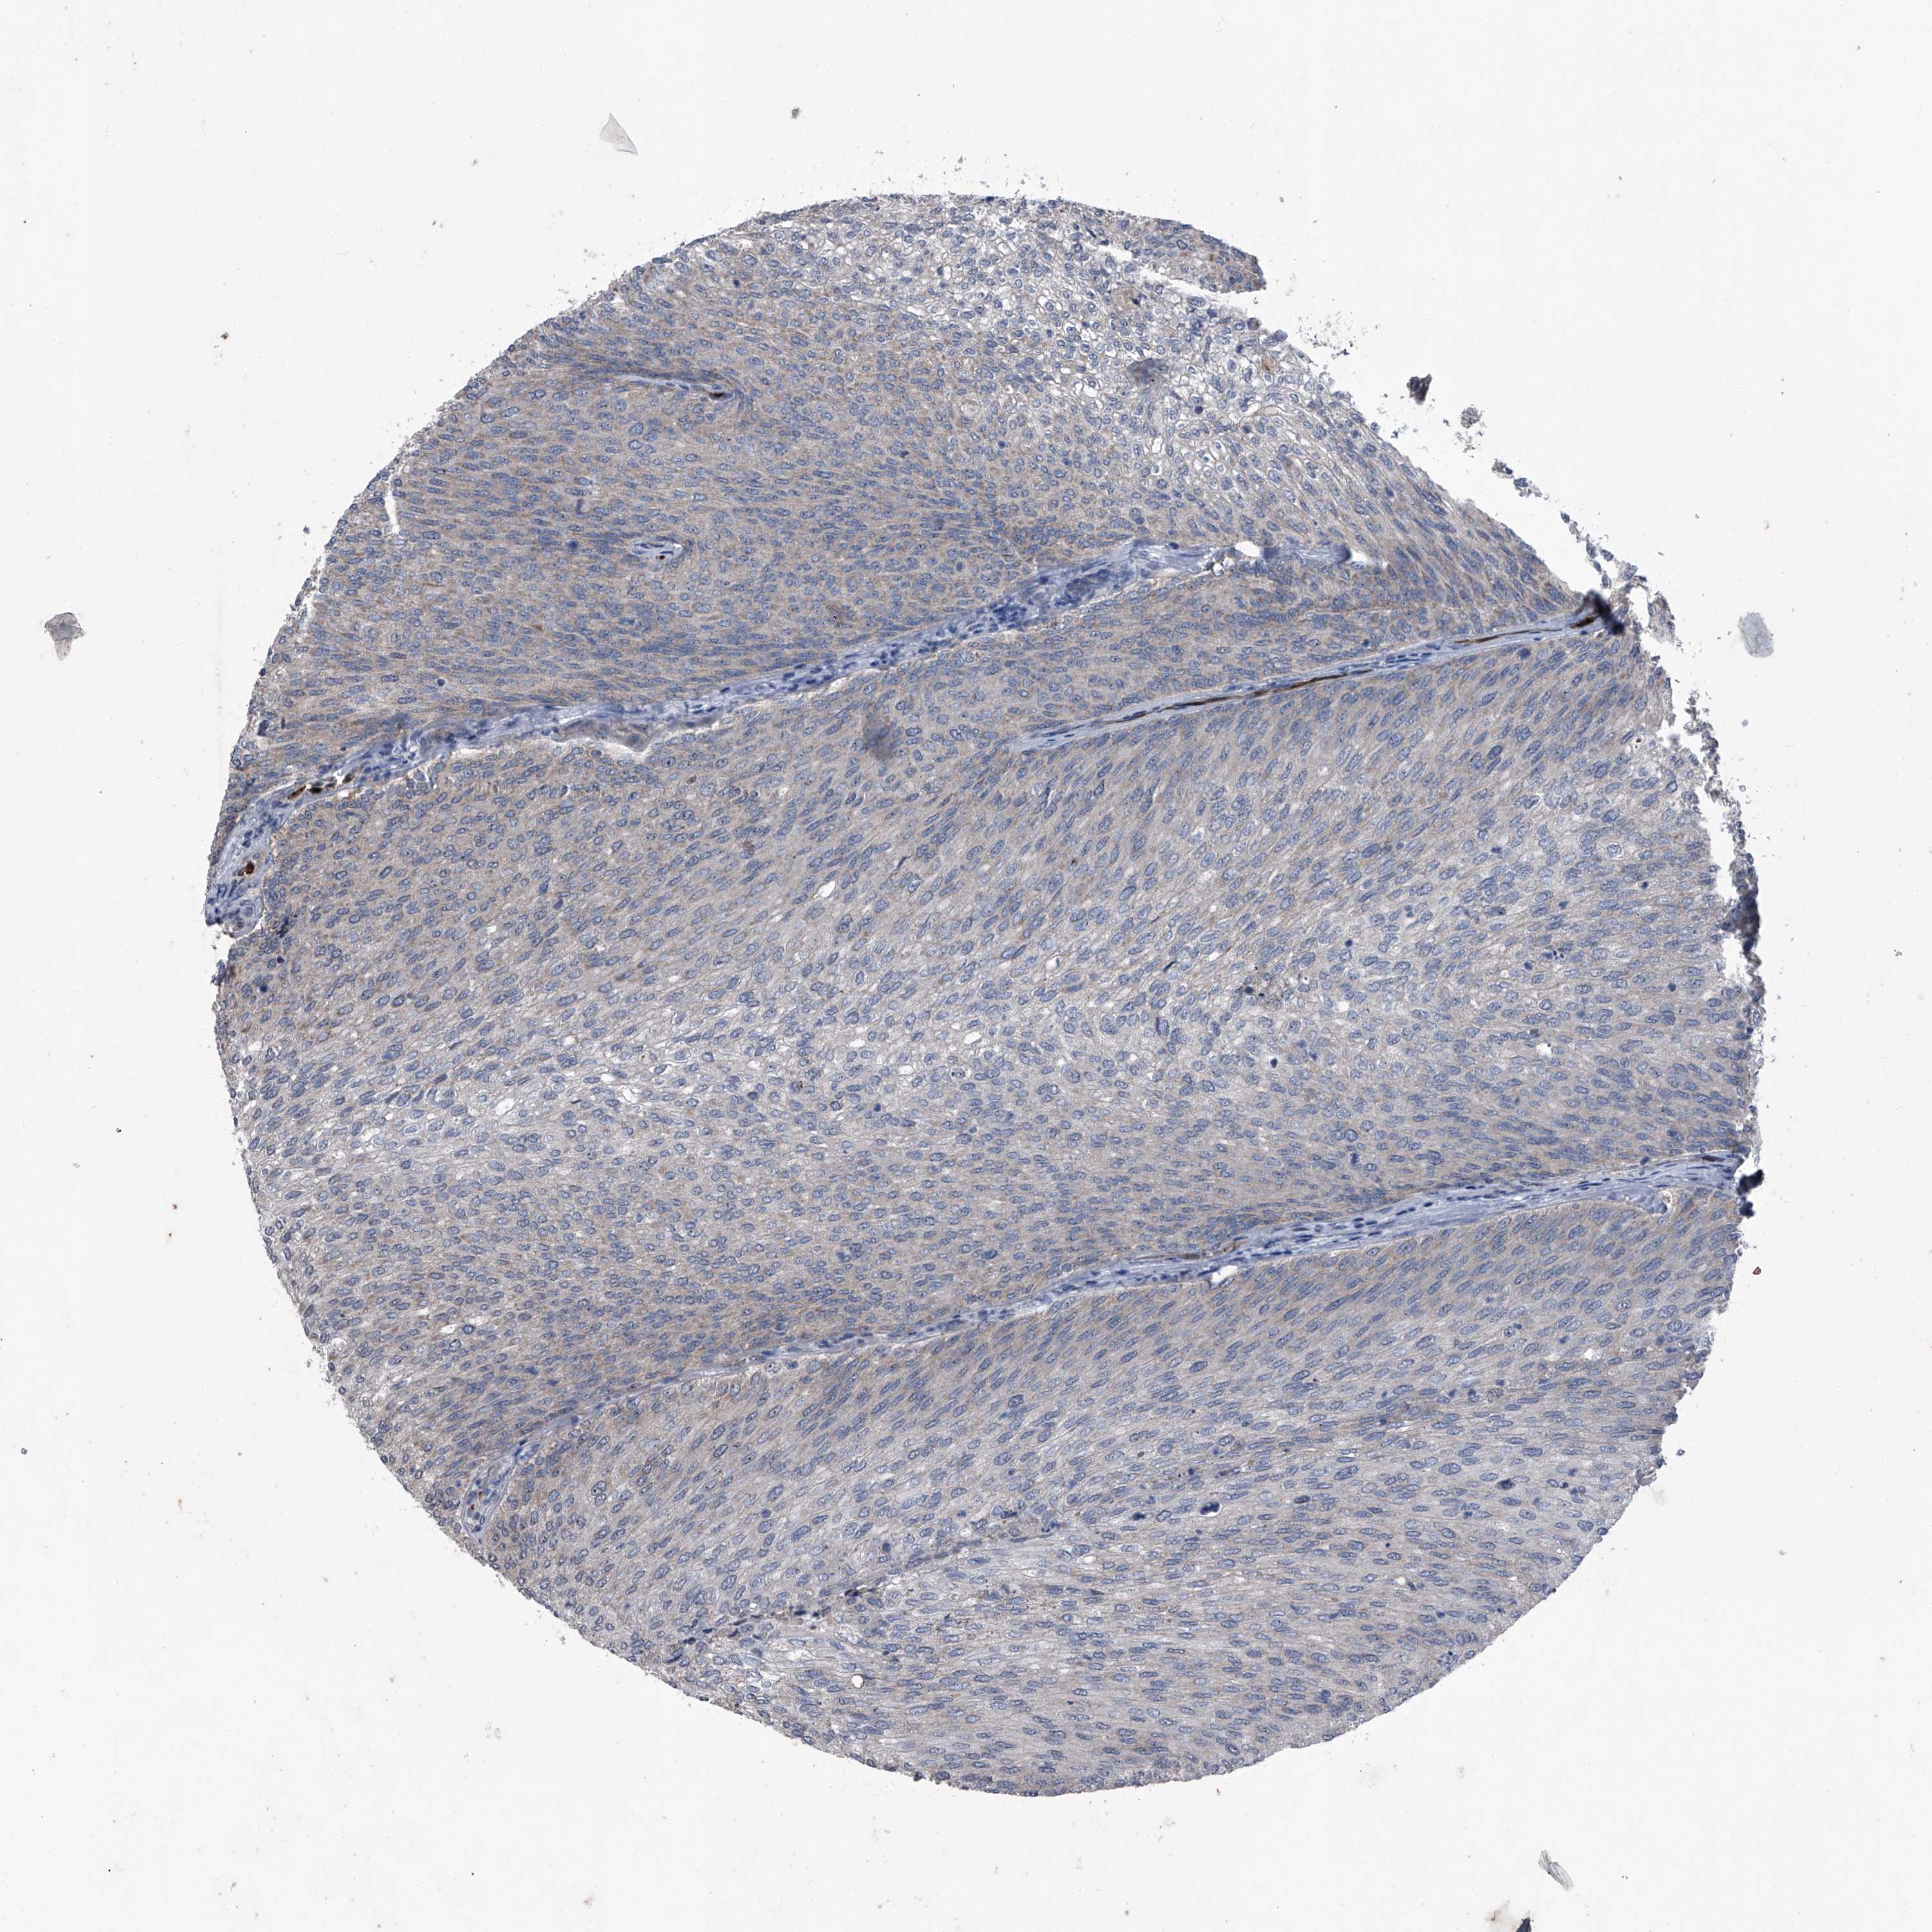

UROTHELIAL CANCER - Protein expressioni

A mouse-over function shows sample information and annotation data. Click on an image to view it in a full screen mode. Samples can be filtered based on level of antibody staining by selecting one or several of the following categories: high, medium, low and not detected. The assay and annotation is described here.

Note that samples used for immunohistochemistry by the Human Protein Atlas do not correspond to samples in the TCGA dataset.

Antibody stainingi

Antibody staining in the annotated cell types in the current human tissue is reported as not detected, low, medium, or high, based on conventional immunohistochemistry profiling in selected tissues. This score is based on the combination of the staining intensity and fraction of stained cells.

Each image is clickable and will lead to virtual microscopy that enables deeper exploration of all samples and also displays staining intensity scores, fraction scores and subcellular localization as well as patient and tissue information for each sample.

Antibody HPA029137

Antibody HPA029138

Antibody HPA029139

Staining

High

Medium

Low

Not detected

Intensity

Strong

Moderate

Weak

Negative

Quantity

>75%

75%-25%

<25%

None

Location

Nuclear

Cytoplasmic/membranous

Cytoplasmic/membranous,nuclear

Urothelial carcinoma, Low grade

Urothelial carcinoma, High grade